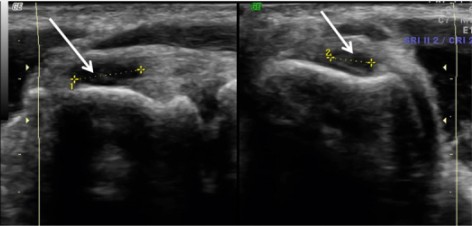

En las imágenes A y B se observa una rotura de la porción profunda del tendón extensor común a nivel del epicóndilo lateral.

La zona marcada con los calipers (cruces y rayas amarillas) corresponde al defecto de la rotura: un área uniformemente oscura donde se ha perdido la continuidad de las fibras tendinosas.

Las flechas continuas señalan zonas sin reflexión fibrilar, es decir, áreas donde ya no se identifica el patrón normal del colágeno. También se aprecia un adelgazamiento localizado del tendón, un dato útil para diferenciar una rotura parcial de una tendinopatía simple.